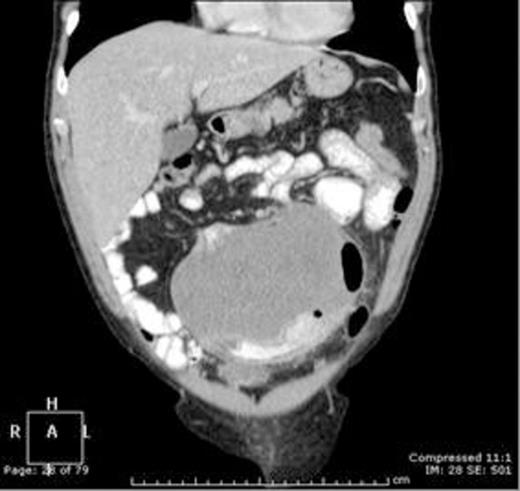

Coronal contrast enhanced CT scan of the abdomen and pelvis demonstrating an homogenous 14.6 x 11 x 14.3 cm intra-abdominal mass closely associated with the small bowel

Computed tomography (CT) (figure 1) showed a large well-defined tumour measuring 14.6 x 11 x 14.3cm arising from the mid-small bowel mesentery and closely associated with, or involving, the small bowel lumen. Abdominal ultrasonography confirmed the lesion to be solid and vascular. Subsequent magnetic resonance imaging (MRI) proved involvement of a jejunal segment and encasement of left-sided branches of the superior mesenteric artery. At laparotomy there was no evidence of synchronous disease. The tumour and associated jejunum with its vascular pedicle was resected in-toto (figures 2,3). Small bowel continuity was re-established with stapled side-to-side primary anastomosis. Post-operative course was uneventful.